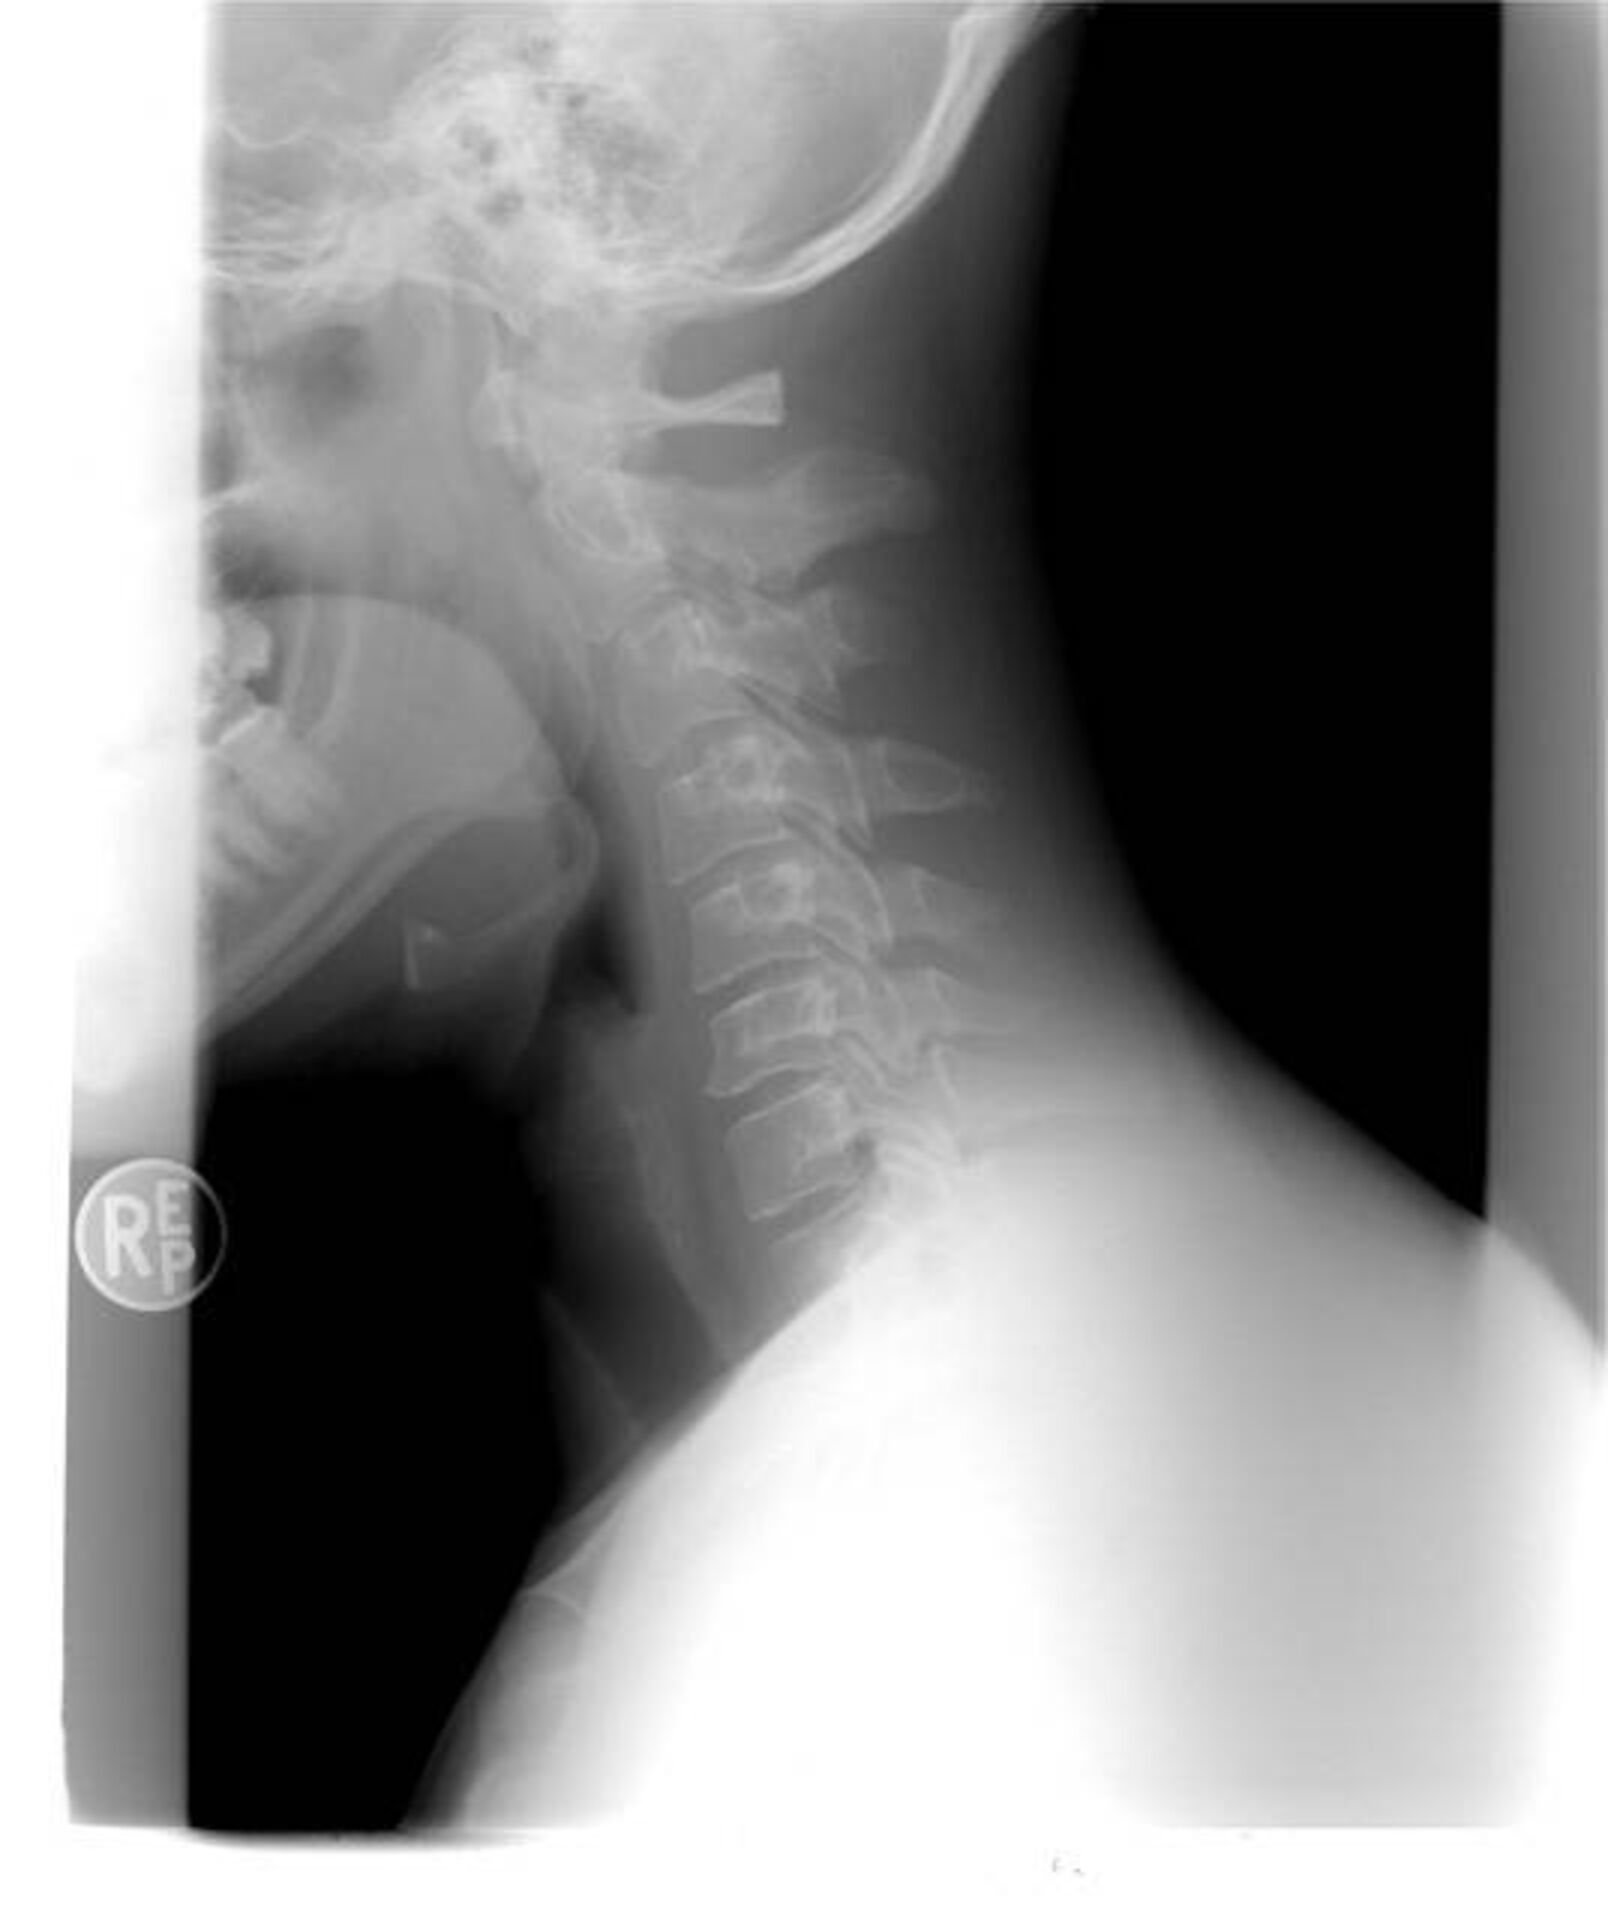

Montants des dommages et intérêts en réparation du coup du lapin cervical subi par un passager de voiture lors d’un accident de la route par le tribunal judiciaire de Toulon

Le passager victime d’un accident de la route en voiture, ayant subi un coup du lapin ou une entorse cervicale, à Toulon, a droit à la réparation de son dommage corporel, sous forme de dommages intérêts.